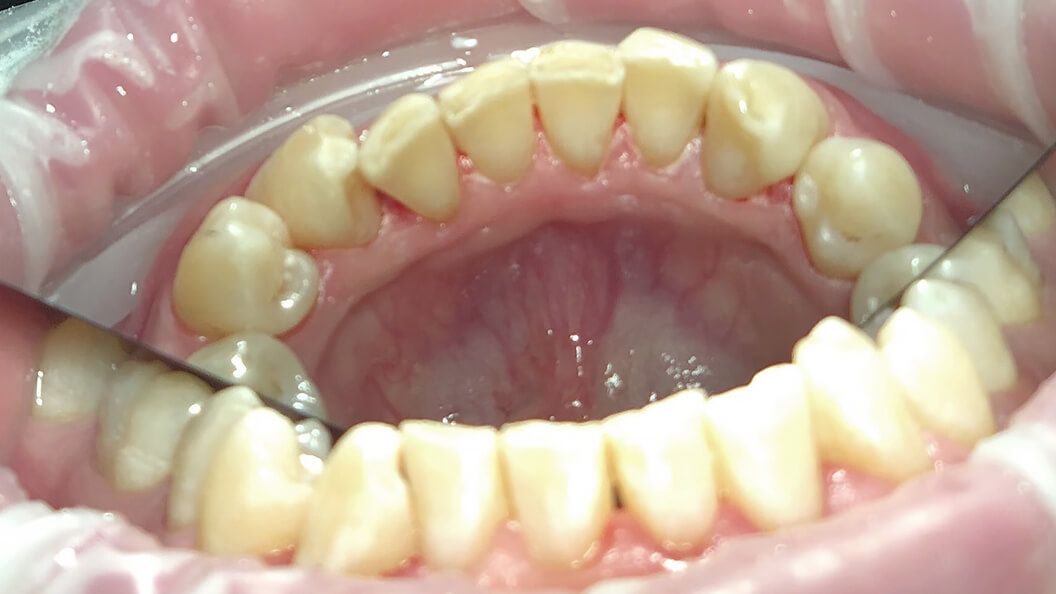

Примеры работ

Профессиональная чистка зубов Prophyflex

В «Стоматологии Комфорта» предлагаем бережную чистку зубных отложений по немецкой системе ProphyFlex (Профифлекс) от компании KaVo Dental Excellence. Мягкий зубной налет и пигментацию эмали вычищаем за 1 посещение. Сеанс длится 30 минут. Технология бережно воздействует на зубы, не повреждая зубную эмаль.